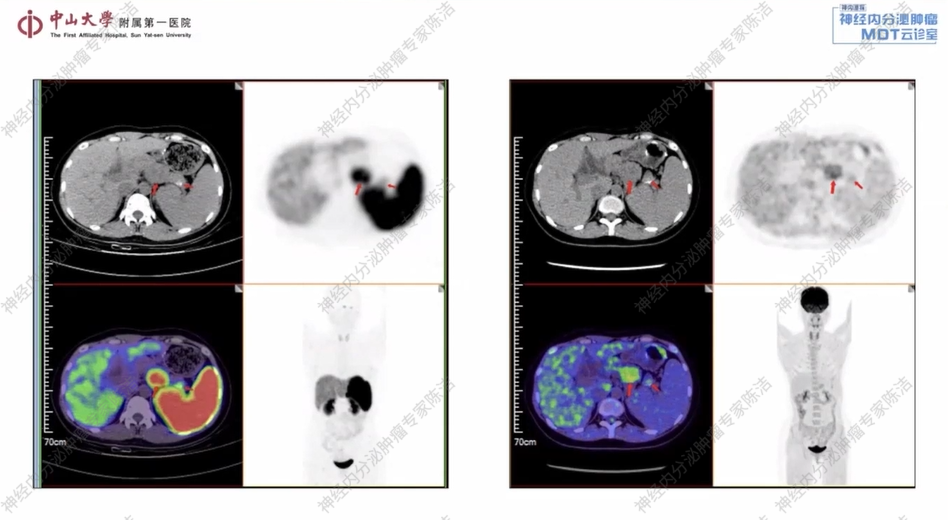

18F-FDG-PET-CT及68Ga-DOTANOC-PET-CT双扫描:1、胰体尾部肿块,生长抑素受体显像强阳性,糖代谢活跃,考虑神经内分泌肿瘤;胰腺尾部结节伴钙化,生长抑素受体显像阳性,糖代谢轻度活跃,考虑神经内分泌肿瘤;胰体多发小囊肿;2、左侧小脑半球结节伴周围水肿,生长抑素受体显像阳性,糖代谢未见明显增高,考虑肿瘤仍具有活性;以上改变可符合VHL综合征;3、外院MRI所示颈髓异常信号区,生长抑素受体显像阴性,糖代谢未见增高,待排血管母细胞瘤;脊髓(胸9、胸12椎体水平)生长抑素受体显像弱阳性,糖代谢轻度活跃,性质待定,待排血管母细胞瘤。

核医学科徐俊彦教授:该患者胰腺体部和尾部各可见一个软组织结节。其中,胰体部结节较为明显,中央密度不均,并伴有部分囊性坏死区;胰尾部结节则周围伴有钙化。PET/CT显示,这些结节均高度表达生长抑素受体,且FDG代谢呈轻度活跃。综合分析,该患者的肿瘤倾向于分化良好,分级不超过G2级别的神经内分泌肿瘤。对于这类SSTR表达阳性的神经内分泌肿瘤,68Ga-PET/CT在明确诊断和分期上具有重要价值。同时,FDG-PET/CT显示肿瘤具有中度糖代谢活性,这与G2的分级相符。双核素显像为疾病的全面评估和诊断提供了关键信息。